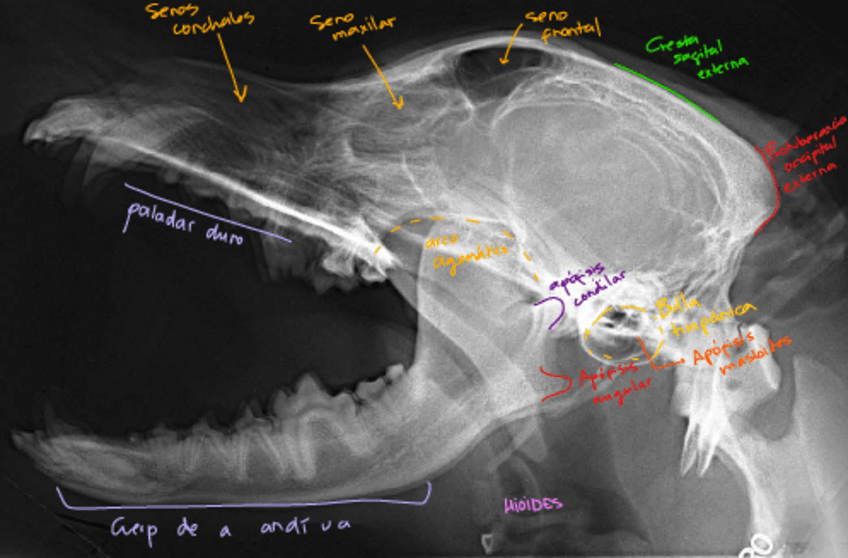

Radiografias-cabeza-perro.pdf

Apuntes - Imagenes-secciones-Resonancia-magnetica-cabeza-perro.pdf